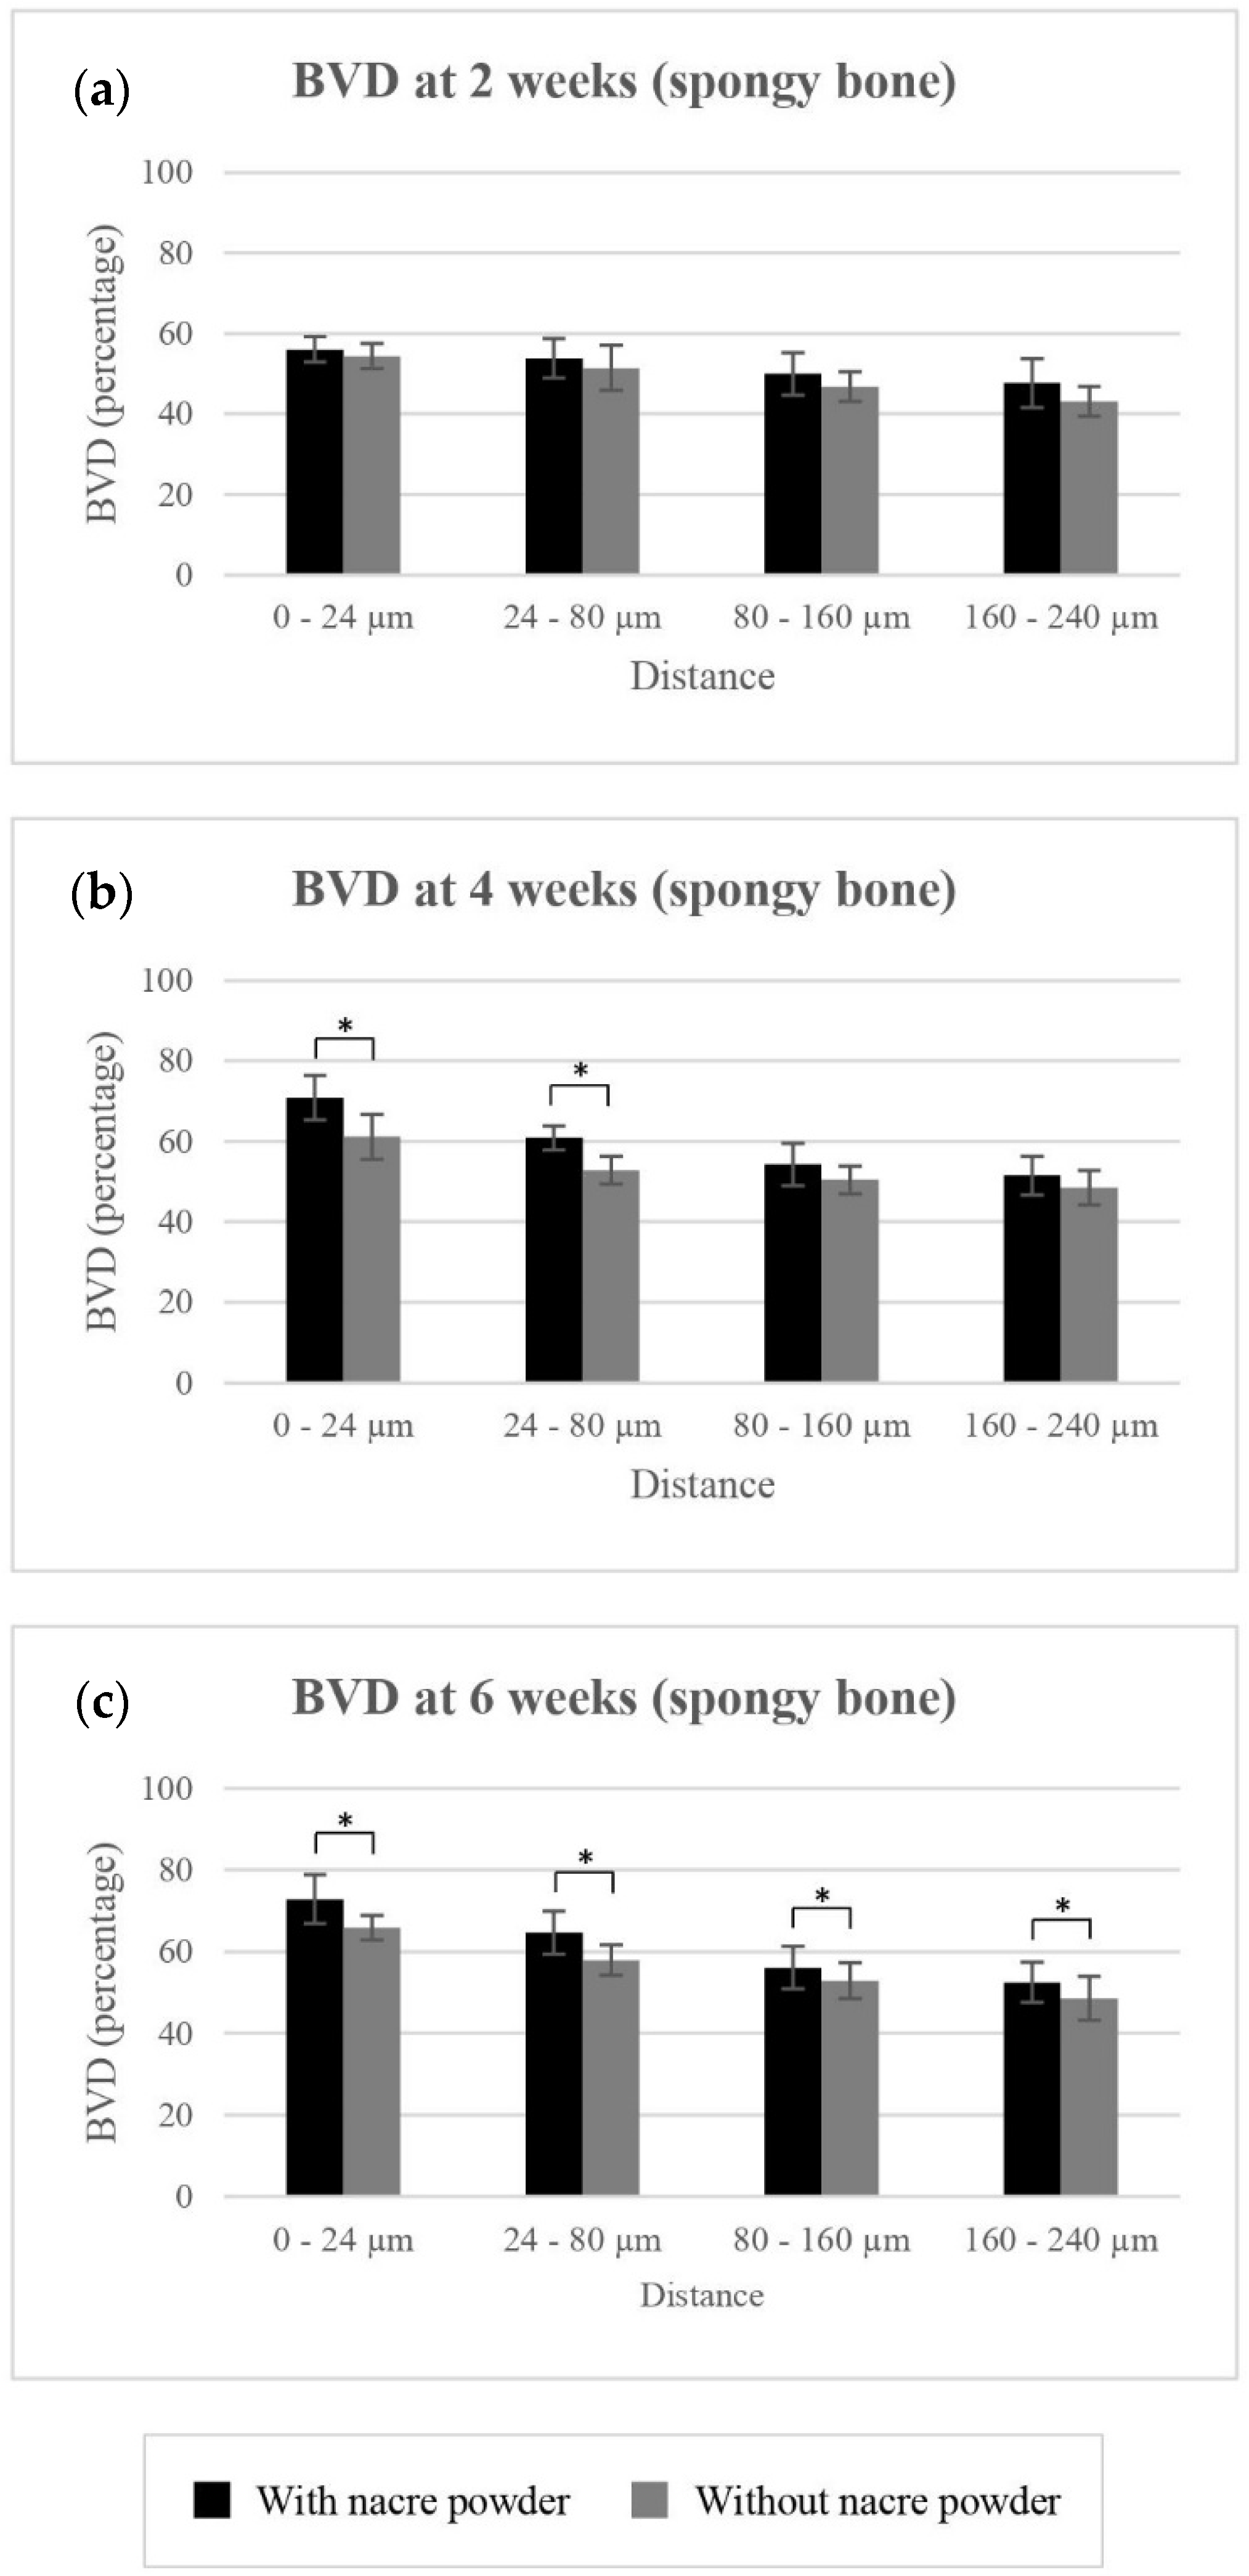

2.2.2. Bone Volume Density (BVD)

BVD of Spongy Bone

| Treatment | |||||||

|---|---|---|---|---|---|---|---|

| Without Nacre Powder (Controls) | With Nacre Powder | ||||||

| Time Points | 2 Weeks | 4 Weeks | 6 Weeks | 2 Weeks | 4 Weeks | 6 Weeks | |

| BVD (%): spongy bone | |||||||

| 0 to 24 µm | 54.36 ± 3.14 | 61.12 ± 5.54 | 65.84 ± 3.02 | 56.02 ± 3.10 | 70.81 ± 5.49 | 72.83 ± 6.01 | |

| 24 to 80 µm | 51.46 ± 5.52 | 52.79 ± 3.45 | 57.89 ± 3.72 | 53.85 ± 4.84 | 60.86 ± 2.98 | 64.64 ± 5.33 | |

| 80 to 160 µm | 46.80 ± 3.72 | 50.45 ± 3.43 | 52.87 ± 4.40 | 49.95 ± 5.27 | 54.23 ± 5.30 | 56.05 ± 5.18 | |

| 160 to 240 µm | 43.15 ± 3.71 | 48.50 ± 4.24 | 48.54 ± 5.30 | 47.65 ± 6.03 | 51.47 ± 4.86 | 52.42 ± 4.89 | |